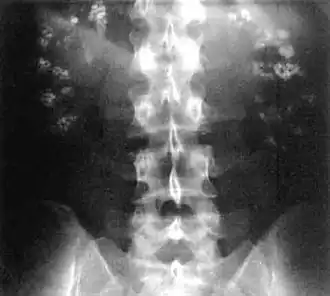

| Bilateral nephrocalcinosis seen on an abdominal x-ray | |

Nephrocalcinosis, once known as Albright's calcinosis after Fuller Albright, is a term originally used to describe the deposition of poorly soluble calcium salts in the renal parenchyma due to hyperparathyroidism. The term nephrocalcinosis is used to describe the deposition of both calcium oxalate and calcium phosphate.[1] It may cause acute kidney injury. It is now more commonly used to describe diffuse, fine, renal parenchymal calcification in radiology.[2] It is caused by multiple different conditions and is determined by progressive kidney dysfunction. These outlines eventually come together to form a dense mass.[3] During its early stages, nephrocalcinosis is visible on x-ray, and appears as a fine granular mottling over the renal outlines. It is most commonly seen as an incidental finding with medullary sponge kidney on an abdominal x-ray. It may be severe enough to cause (as well as be caused by) renal tubular acidosis or even end stage kidney disease, due to disruption of the kidney tissue by the deposited calcium salts.